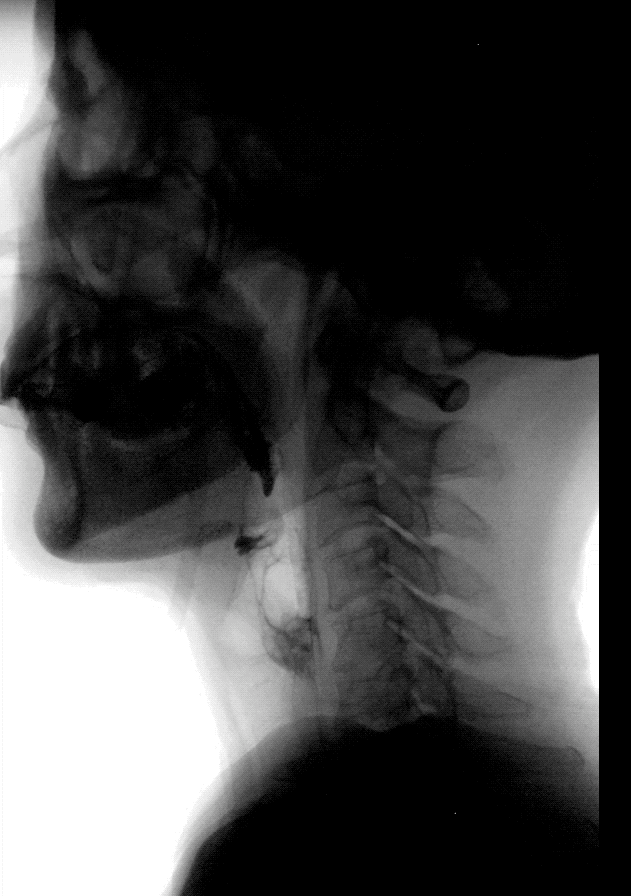

正常吞咽功能下的吞咽造影检查